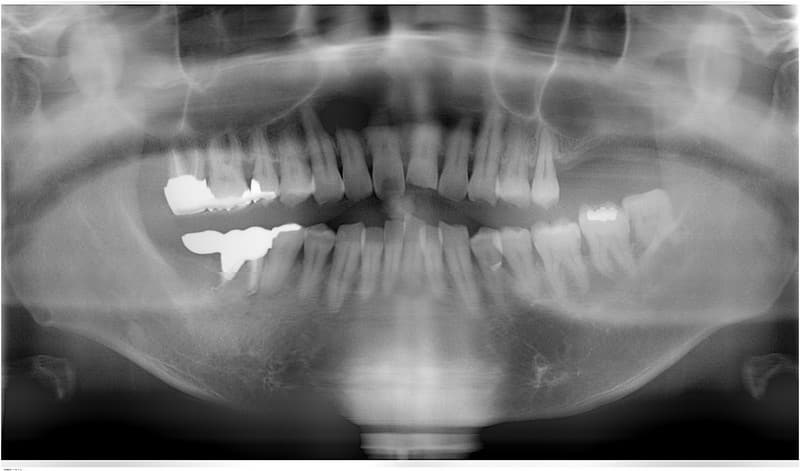

インプラント治療の流れ

インプラント治療に関する相談と説明

病歴や健康状態に関する問診、口の中の検査、レントゲン写真や歯型の採取

治療方針、計画の決定と説明

- 外科処置によって顎の骨にインプラントを埋め込みます。

- 3~6ヶ月後にインプラントに人工の歯を連結するためのパーツを取り付けます。

(小外科処置を伴います。)

技工士さんがあなただけの人工の歯をカスタムメイドで製作します。

人工の歯をインプラントに連結して完成となります。